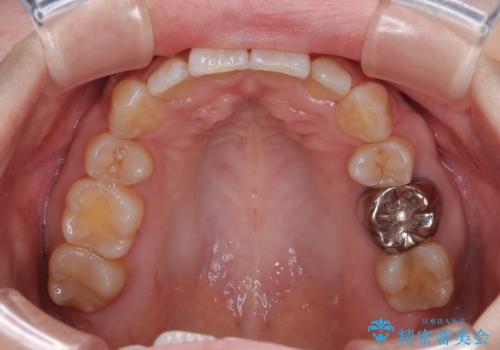

第二小臼歯抜歯としたため、治療期間は長くなりましたが、満足のいく仕上がりとなりました。

上顎は左右の第一小臼歯2本を、下顎は左右の第二小臼歯2本を抜歯して、口元が突出しないようにしながら、奥歯の咬み合わせを改善していく治療計画としました。